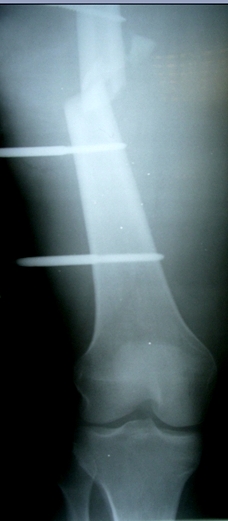

Больной 27 лет, мотоциклист. Поступил 23.04.10

ДЗ. О. перелом н.з левого бедра Gustillo 3b (c повредрение бедренной вены),

О.Правого бедра Gustillo 2, з. фрагментарный перелом левой голени.

При поступлении Hb 66 ISS 40, фиксация стержневыми аппратами, сосудистые

хирурги выполнили шов вены. Выполена резекция бедренной кости 9 см

В настоящий момент планируем. Переход со стержневых аппаратов на стержни с

антибактериальным покрытием на правом бедре и левой голени.

Левое бедро пранируем продолжить фиксировать в стержневом аппрате.

Вопрос: что делать с левым бедром? Учитывая внутрисутавной характер

перелома, дефект бедра 9 см.